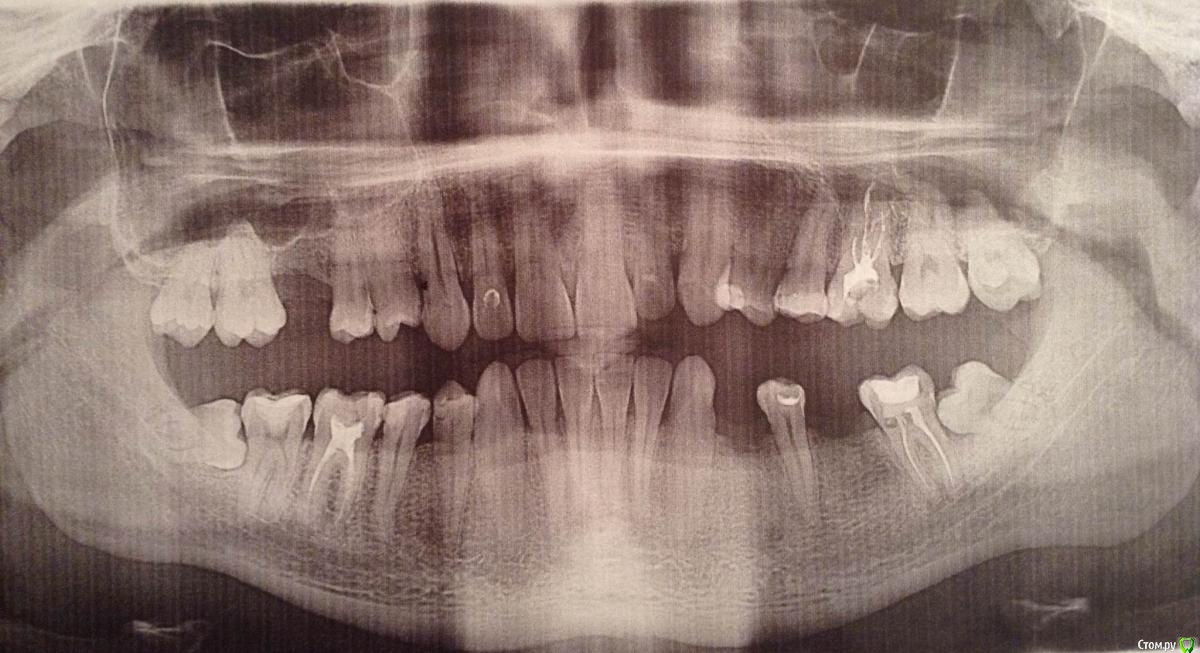

abc32 Опубликовано 16 апреля, 2019 Поделиться Опубликовано 16 апреля, 2019 Здравствуйте. Требуется перелечить корни левой нижней 7ки (на снимке справа), часть зуба отвалилась, на одном из корней сломан инструмент. Врач сказал, что нужно удалять сначала 8ку.На завтра уже назначено удаление восьмого зуба. Сегодня мне пришла мысль в голову, что может возможно удалить плохую 7ку, а на ее место ортодонтически перетянуть вроде как хорошую 8ку. С врачом это не обсуждали, к ортодонтам тоже не успел сегодня попасть. Надеюсь, еще успеют на форуме подсказать как лучше. Или это глупая затея? Если перетаскивание возможно, то сколько это займет времени и примерных денежных трат? Стоит ли оно того? Беспокоит, что удалю 8ку, с семеркой возникнут проблемы, она долго не продержится, и ее все равно придется удалить. Таким образом, лишусь обоих зубов.Спасибо, надеюсь, что посоветуете что-нибудь. Ссылка на комментарий